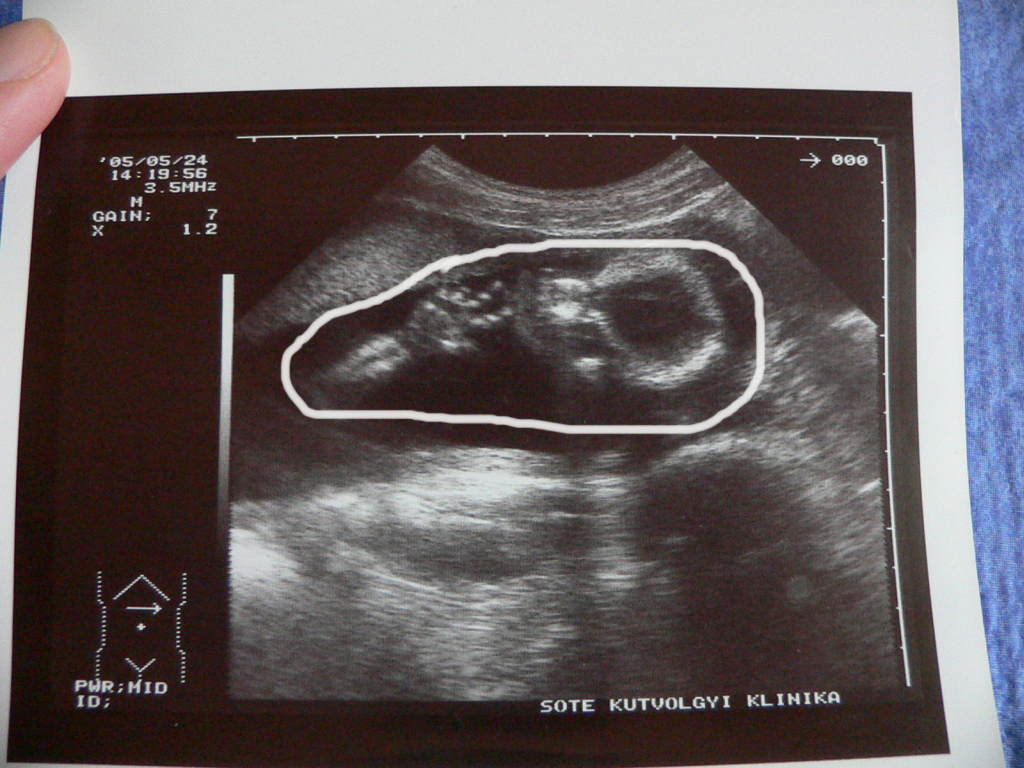

| itt pedig oldalnézetből és a köldökzsinór is látható. | |